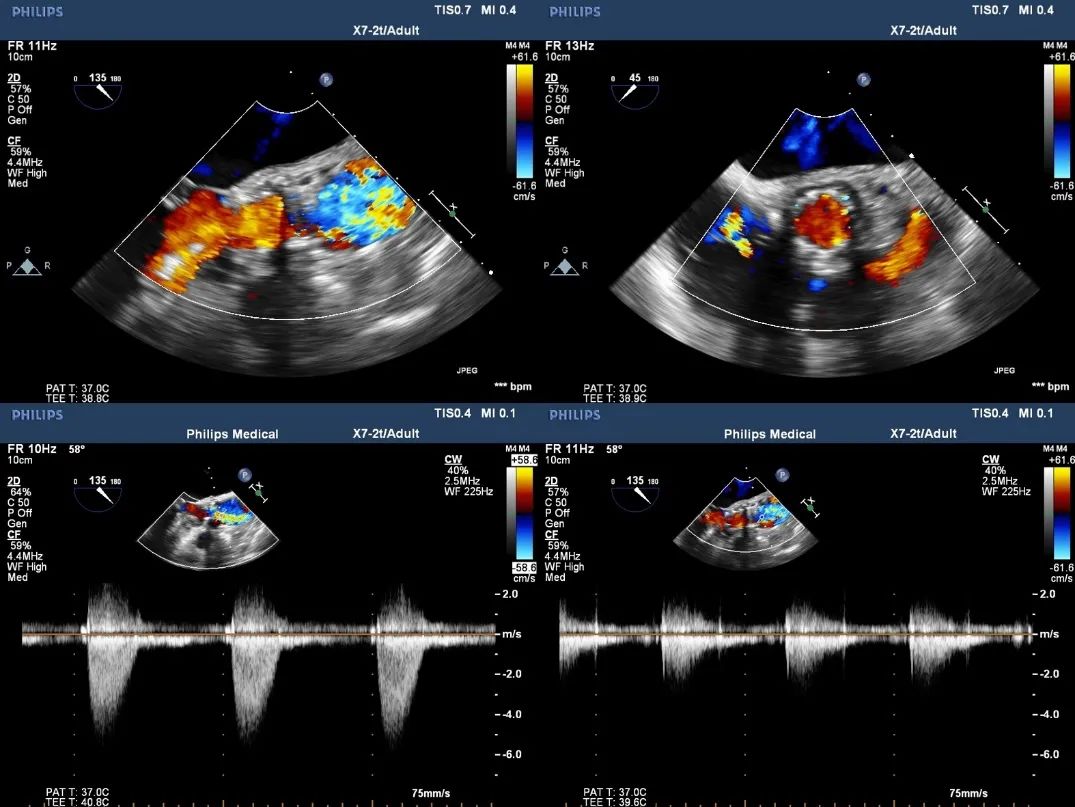

超声影像

瓣膜工作状态良好,极微量瓣周漏

Vmax 1.75m/s,PG 14mmHg

TEE影像,烟囱支架显影清晰,支架内血流通畅